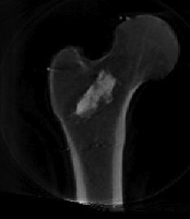

3D Volumetric and Biomechanical Models of the Proximal Femur from DXA Projection ImagesThis project combines development of a statistical atlas of the proximal femur with deformable 2D-3D registration to create patient-specific "virtual CT" volumetric models based on a small number of Dual-Energg X-ray (DXA) images. One potential application of this work would be biomechanical modeling to assess fracture risk of patients undergoing DXA screening. Primary funding: Hologic |

Robotic Bone AugmentationThe long-range goal of this project is to develop an image-guided workstation with biomechanical planning and intraoperative updates for surgical interventions applied to osteoporotic bone augmentation, when the risk of bone fracture becomes imminent. Specifically in this proposal, we demonstrate the feasibility of bone augmentation by developing a surgical system for femur augmentation Primary funding: NIH R21 |